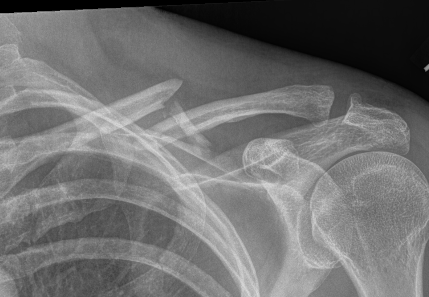

Compound clavicle fracture

Shorted / displaced midshaft clavicle fractures

Z shaped midshaft clavicle fracture